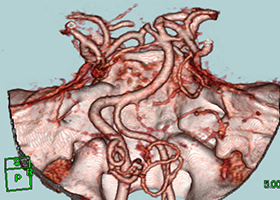

造影三次元CT画像

左前頭側頭開頭で動脈瘤クリッピング術を行った。手術中は脳血管撮影装置を用いたHybrid手術を施行し、動脈瘤の消失を手術中に確認する。

造影3DCT検査:錐体斜台部巨大髄膜腫認め

神経や血管を巻き込んでいます。 -